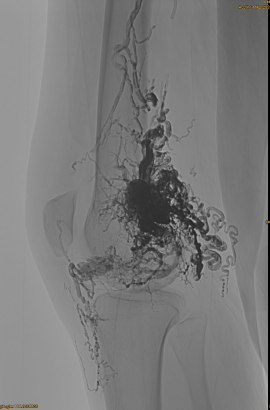

Začetni DSA:

Končni rezultat:

Komaj kakšen venski odtok:

Pozno faza, potrebna je še ena EMBO, vendar veliko bolje: